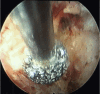

Surgical treatment of the degenerative disc disease has evolved from traditional open spine surgery to minimally invasive spine surgery including endoscopic spine surgery. Constant improvement in the imaging modality especially with introduction of the magnetic resonance imaging, it is possible to identify culprit degenerated disc segment and again with the discography it is possible to diagnose the pain generator and pathological degenerated disc very precisely and its treatment with minimally invasive approach. With improvements in the optics, high resolution camera, light source, high speed burr, irrigation pump etc, minimally invasive spine surgeries can be performed with various endoscopic techniques for lumbar, cervical and thoracic regions. Advantages of endoscopic spine surgeries are less tissue dissection and muscle trauma, reduced blood loss, less damage to the epidural blood supply and consequent epidural fibrosis and scarring, reduced hospital stay, early functional recovery and improvement in the quality of life & better cosmesis. With precise indication, proper diagnosis and good training, the endoscopic spine surgery can give equally good result as open spine surgery. Initially, endoscopic technique was restricted to the lumbar region but now it also can be used for cervical and thoracic disc herniations. Previously endoscopy was used for disc herniations which were contained without migration but now days it is used for highly up and down migrated disc herniations as well. Use of endoscopic technique in lumbar region was restricted to disc herniations but gradually it is also used for spinal canal stenosis and endoscopic assisted fusion surgeries. Endoscopic spine surgery can play important role in the treatment of adolescent disc herniations especially for the persons who engage in the competitive sports and the athletes where less tissue trauma, cosmesis and early functional recovery is desirable. From simple chemonucleolysis to current day endoscopic procedures the history of minimally invasive spine surgery is interesting. Appropriate indications, clear imaging prior to surgery and preplanning are keys to successful outcome. In this article basic procedures of percutaneous endoscopic lumbar discectomy through transforaminal and interlaminar routes, percutaneous endoscopic cervical discectomy, percutaneous endoscopic posterior cervical foraminotomy and percutaneous endoscopic thoracic discectomy are discussed.